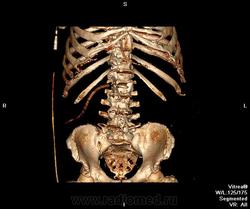

Пациент оперирован по поводу аденоКа толстого кишечника, гемиколэктомия. Онкопоиск, поиск вторичного поражения.

В воротах печени беда, но не об этом сейчас. Прицельно смотрим контраст.

Случай 2. Опять не попали в фазы, рано. Исследование малоинформативно по сути(. Какова скорость введения автошприцем? Катетер кубитальный или в запястье?